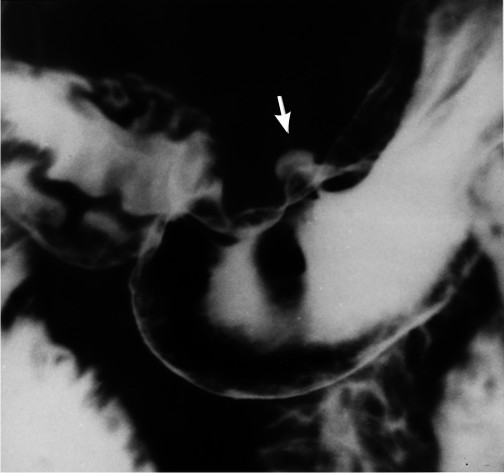

- рвотный центр в дорсальной части латеральной ретикулярной формации и

- хеморецепторная триггерная зона в самом заднем поле ромбовидной ямки (area postrema) на дне четвертого желудочка .